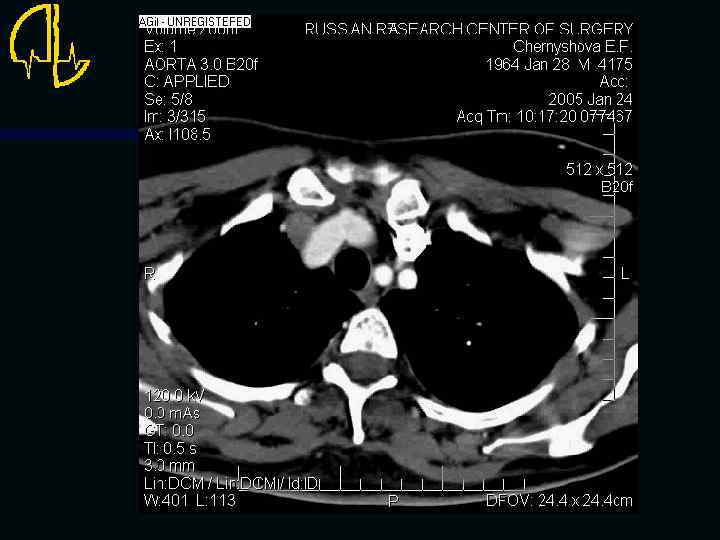

Исследование сосудов грудной клетки